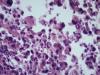

Опухоль легкого |

Карциноид...

Аденокарцинома со стелющимся типом роста (lepidic)

Тоже склоняюсь к бронхиолоальвеолярному раку.

Уважаемый Медик, добрый вечер! Поясните, пожалуйста, в чем существенная разница между БАР и предложенным мной вариантом? В своей работе я использую классификацию 2015 года, в которой БАР нет, это устаревший термин. Верно, с 2015г..БАР нет. В данном случае Аденкарцинома, lepidic тип👏 |